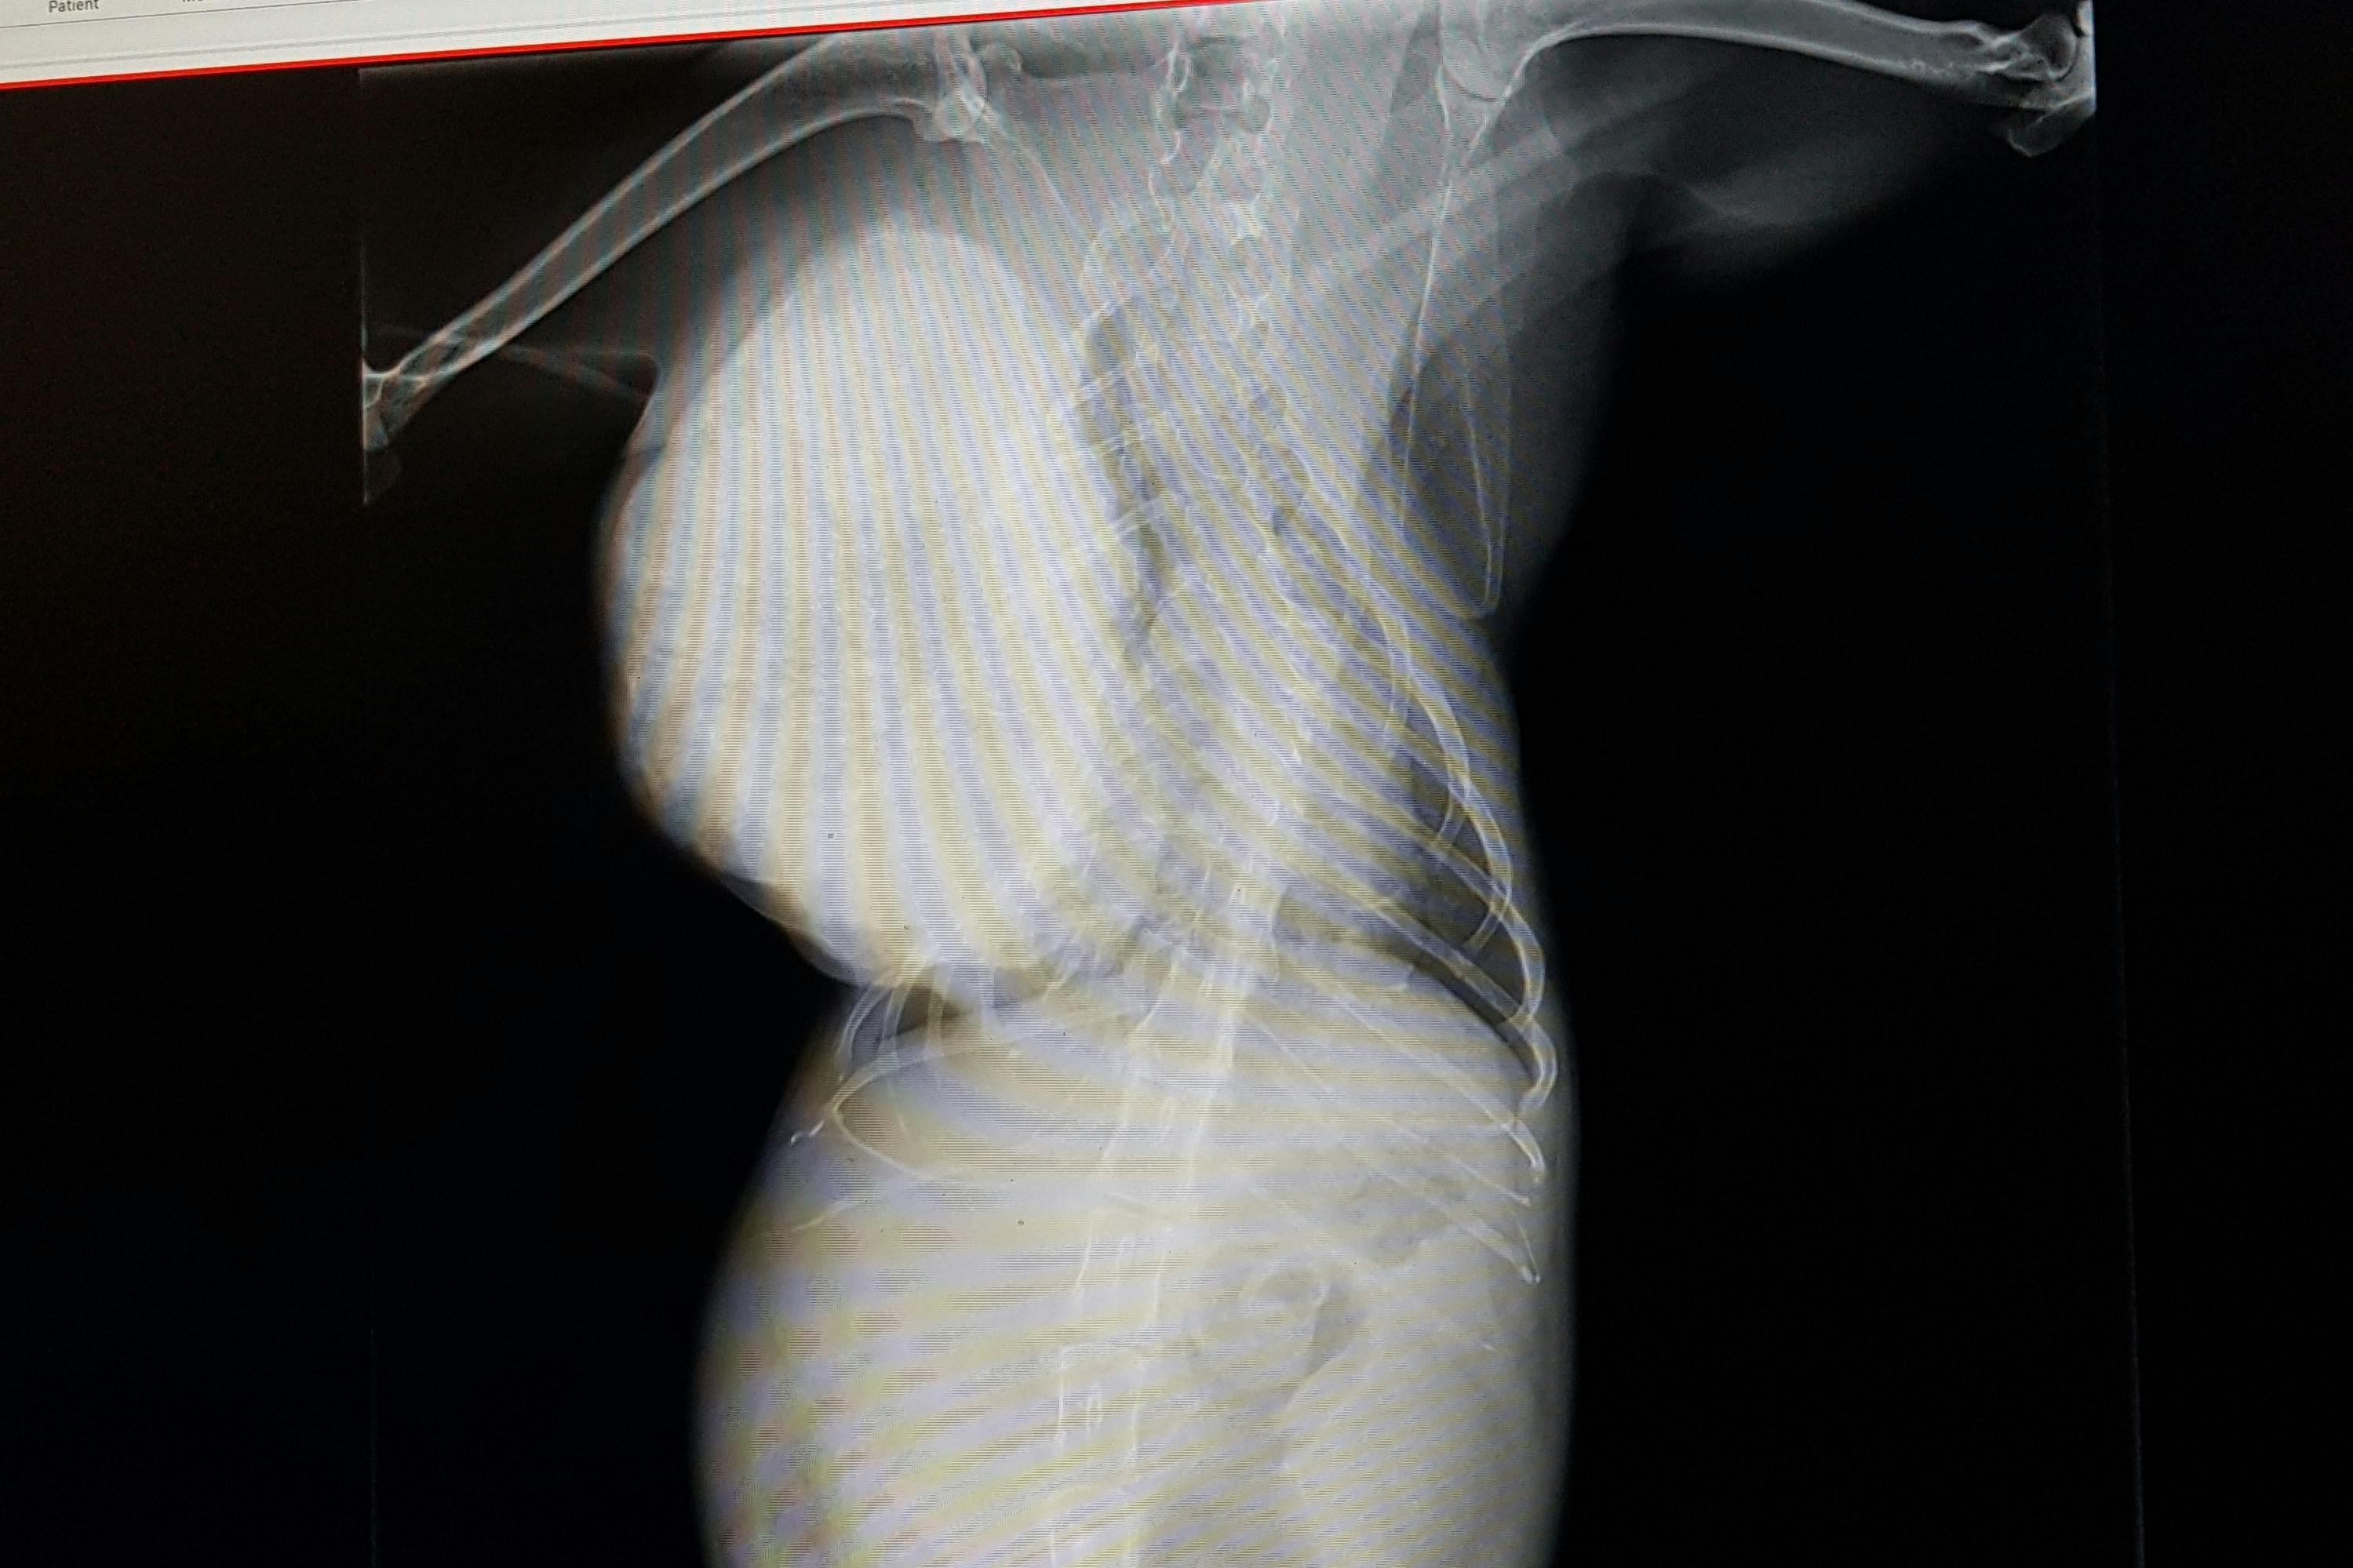

猫には前例がないほどの大きな骨肉腫で、放っておくと肺が圧迫され息ができなくなり亡くなってしまいます。

検査、CTで約14万円、手術や入院で約50万円。腫瘍、肋骨を取る大きな手術になります。手術後の経過によってはそれ以上かかることもあるそうです。根治は難しいそうですが、少しでも長く生きて最期は幸せにしてあげたいと思っています。

骨肉腫の野良猫ちゃんの検査、CTで約14万円。

手術 入院費 約50万 その後定期的な検診。活動報告の方で、経過報告や領収証もお載せします。